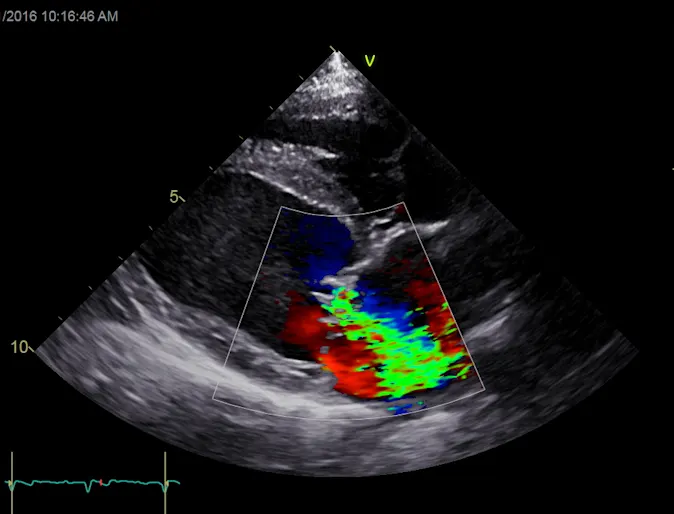

What Is An Echocardiogram?

An echocardiogram (ultrasound of the heart) uses ultrasound waves to create real time images that allow the cardiologist to evaluate the heart size, valve function and heart strength. Most people are familiar with ultrasound technology that is used for a pregnancy sonogram.